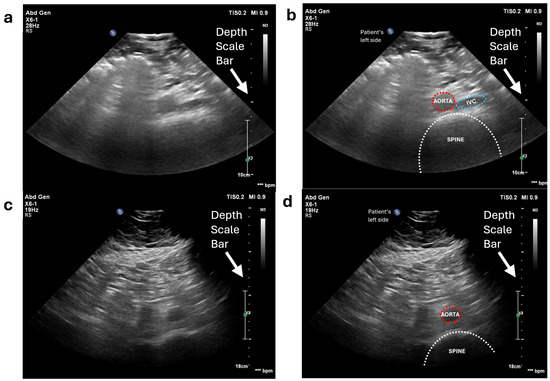

Unlike scanning a phantom, which contains only two vessels and is composed of materials specifically designed for ultrasound imaging, the anatomy of the human abdomen is far more complex and varies between individuals. Therefore, the initial step is to locate the abdominal aorta or the common iliac arteries for each volunteer. To achieve this, we performed a freehand ultrasound scan. The scan is conducted exclusively in the transverse plane (where the aorta appears as a circular structure in the ultrasound image), as the diameter of the aorta is a critical criterion for detecting aneurysms. We initially positioned the probe on the volunteer’s abdomen, several centimetres to the left of the umbilicus. In the resulting ultrasound image, the top corresponds to the volunteer’s skin surface, while the bottom represents the spine and posterior structures. There are a number of key features used to identify the aorta. It appears as a circular structure with bright walls and a dark lumen. This is distinguished from the inferior vena cava (IVC), which has thinner walls and therefore appears less bright. The IVC is also less circular than the aorta due to the thinner walls and reduced intraluminal pressure (Figure 12a). This distinction can be further confirmed by the pulsing motion observed in B mode in the aorta, which is particularly clear in slimmer individuals. The pulsatile nature of the aorta can also be demonstrated with colour and spectral Doppler (Figure 12b), which contrasts to the respiratory modulated phasic flow demonstrated in the IVC. Anatomically, the aorta is situated just superficially to the spine, and to the left of the IVC. The spine appears as a curved structure at the bottom of the image, with a bright boundary and dark interior. Throughout this process, the sonographer must also adjust the ultrasound machine settings, including gain, depth, and focus, to optimize the image quality. These parameters are patient-specific and are carefully fine-tuned to ensure clear visualization of the aorta and surrounding structures.

Figure 12.

Abdominal aorta and iliac artery localization in volunteer testing: (a) B−mode image of the abdominal aorta annotated by a clinical vascular scientist (Volunteer 1) and (b) pulsed wave Doppler of the iliac artery (Volunteer 2).